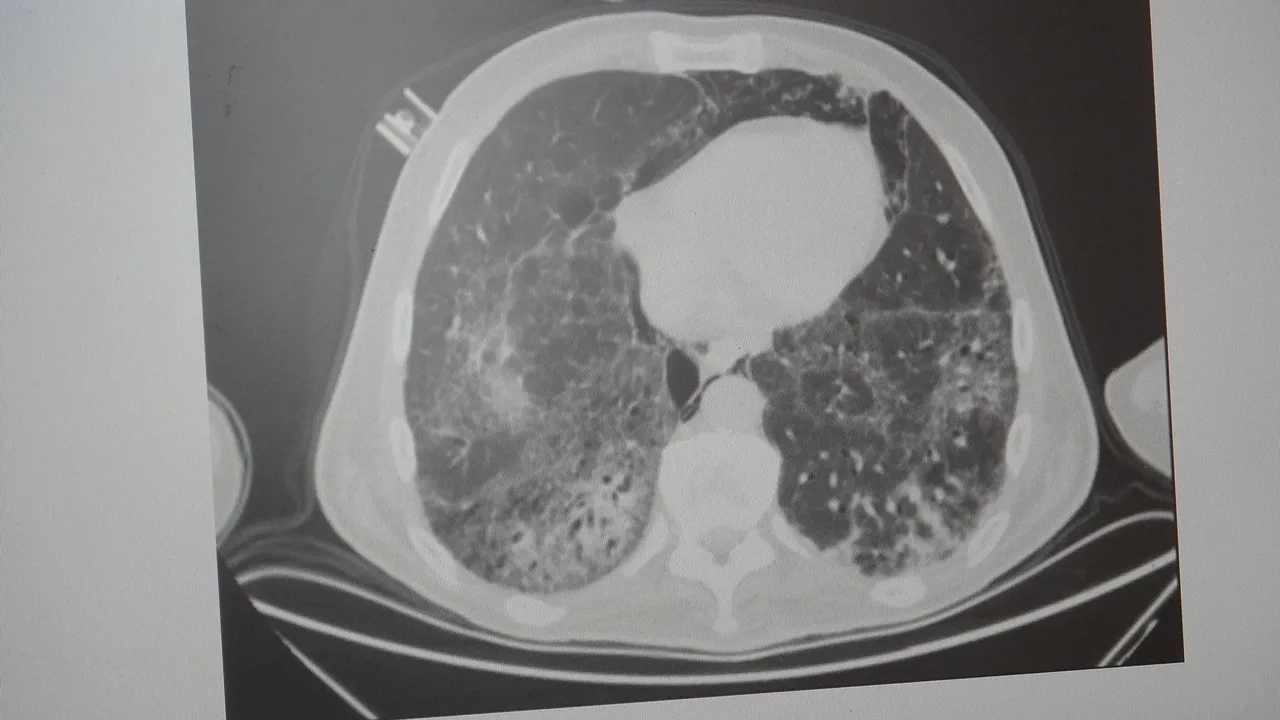

KOAH toplumda sık görülen bir hastalıktır ve yaklaşık toplumda bunu yüzde 10 civarında görüyoruz. KOAH, zararlı maddelerin akciğeri parçalamasıyla oluşan bir rahatsızlık ve bunun da en önemli nedeni sigara. Vakaların aşağı yukarı yüzde 85’i sigara kullanımından kaynaklıdır. Bunun dışında hava kirliliği, iş yerlerinde kimyasal maddelere maruz kalma ve enfeksiyonlar da yine KOAH'ın nedenleri arasındadır. KOAH'ın önemi şu; bugün Dünya Sağlık Örgütü'nün (DSÖ) dünyada insanları öldüren hastalıklar listesinde ilk 10'da 4'üncü sırada yer alıyor.

Karakurt, KOAH’ın akciğer dokusunu tahrip eden bir hastalık olduğunu ve bu nedenle de hastaların enfeksiyona açık hale geldiğine dikkat çekti:

Akciğer dokusunun tahrip olduğu her durumda hastaların enfeksiyona karşı eğilimi artar ve enfeksiyona yakalandıkları zaman bunun geçmesi güç olur. KOAH'lı hastalar zatürre geçirdikleri zaman öksürük ve balgam artışı gibi birtakım belirtiler gelişir. Ayrıca ateşin 38,5 derecenin üstüne çıkması, nefes darlığının artması, titremeyle birlikte ateşin yükselmesi ve bir takım bilinç bozukluğu gibi belirtiler hastanın zatürre olduğunu gösterebilir. Bu nedenle hastaların erkenden doktora başvurmaları önemlidir.

Bronşit daha çok hava yollarının yani bronşların iltihaplanmasıdır. Zatürre ise hava yollarının uçlarında bulunan ve karbondioksit değişimini sağlayan alveollerin yani hava keselerinin iltihaplanmasıdır. Bronşitten ölüm pek görülmez ama zatürre tehlikelidir; aşağı yukarı yüzde 10 gibi bir ölüm oranıyla seyreder ve bu ölüm oranı yaş arttıkça artar. Ayrım için ateşin yüksek olup olmamasına ve hastada bilinç bozukluğu, solunum sayısının artması ve morarma gibi belirtiler görüldüğü takdirde zatürre olabileceğini düşündürür. Bu gibi durumlarda en kısa zamanda bir sağlık kuruluşuna başvurmak gereklidir.